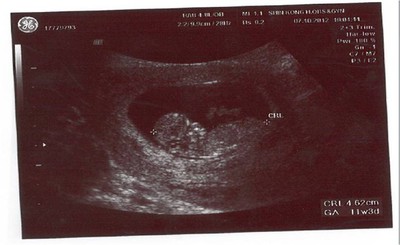

For my baby - 10/12 健康 12W2D

11W3D.jpg星期日媽媽領到了期盼已久的「孕婦健康手冊」,爸爸開心的一直翻一直翻,其實我不太清楚爸爸在翻什麼。但他似乎很在意能不能領到。雖然爸爸不說,但媽媽其實可以感覺到爸爸對乖乖滿滿的愛。有時候...